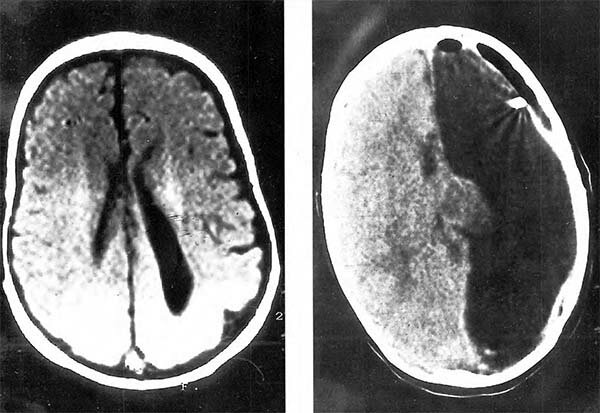

• Primer cirugía de epilepsia

Primer cirugía de epilepsia

Se originó el primer caso de cirugía para la epilepsia en un paciente donde Ferrier fue el arquitecto principal